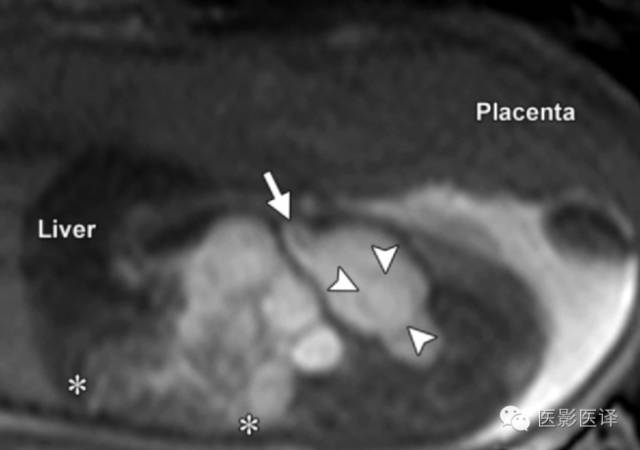

胆管囊肿

胆管囊肿是由于胆胰管连接部畸形所致的肝外或肝内胆管扩张。表现为右肝下间隙上份的单房囊肿,同肝被膜相邻。如果囊性肿物与入肝的扩张胆管直接相通,则可确诊胆管囊肿(图18)。磁共振成像能够更好的评价囊肿与扩张胆管、胆囊和肝脏的关系。如胆管囊肿没有切除,则产后并发症包括恶变、胆管炎和胰腺炎。胆道受累可以排除卵巢囊肿。

图18.胆管囊肿。(a)孕32周超声斜冠状位显示一个卵圆形囊性结构,有分支从肝实质进入该囊性结构。分支位于肝内,囊肿与肝实质关系密切,与胃壁有清楚的分界。(b)插图显示一个胆管囊肿的典型位置与解剖关系。